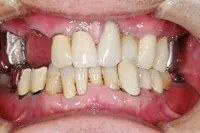

■治療前

■治療後

| 主訴 | しっかりかみたい(咬合障害) |

| 治療方法 | 費用を抑える為、全てインプラントではなく、インプラントを土台とした入れ歯の治療 |

| 治療期間 | 約6か月 |

| 通院回数等 | 約20回 |

| 費用 | 約150万円 |

| リスク・副作用 | 術後の腫れ・痛み |